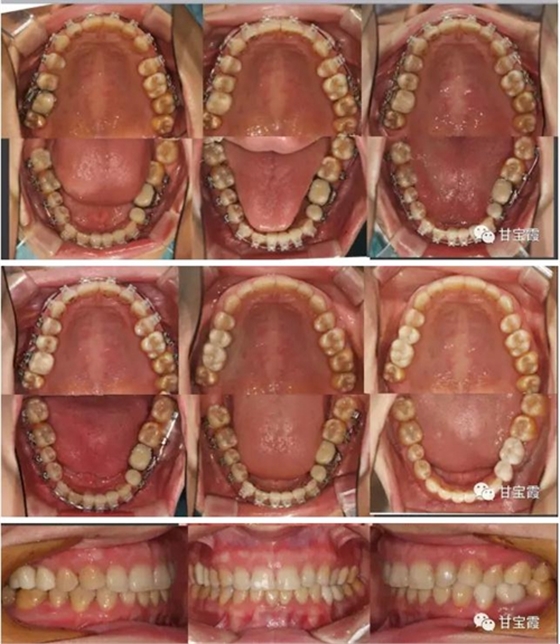

大家都知道以前缺一顆牙要鑲?cè)w烤瓷牙,缺兩顆要鑲六顆烤瓷牙,因而好好的一顆牙就因?yàn)殍偲渌辣荒サ袅艘粚樱挚上?。這次就診根據(jù)患者口腔的檢查我制定了一個(gè)治療計(jì)劃:拆除九顆烤瓷牙,缺牙的部分用正畸的方法移動(dòng)牙齒,關(guān)閉缺牙間隙,不再鑲牙。下前牙的三顆聯(lián)排的烤瓷牙改成單顆修復(fù),這樣更符合生理。下面的系列圖片是治療過(guò)程,大家可以看到缺牙間隙是怎么一點(diǎn)一點(diǎn)關(guān)閉的。

經(jīng)過(guò)28個(gè)月的矯正,大家可以看到原來(lái)的兩個(gè)缺牙間隙沒(méi)有了,舊的烤瓷牙換成了全瓷冠修復(fù)。下面的圖片是矯正前后的X線(xiàn)對(duì)比,